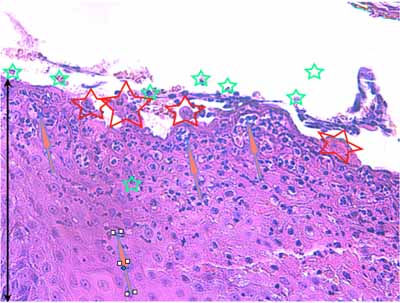

Photo 8 (Hémalun Eosine X 40) : L’épiderme est parsemé de vésiculo-pustules sous-cornées,

extensives, planes, dont le toit, composé de fines lamelles de kératine orthokératosique, est fragile.

Le derme montre un infiltrat de topographie péri-vasculaire.

Le patron lésionnel est celui d’une dermatite psutuleuse sous-cornée périvasculaire.

Légendes de la Photo 8 :

- Pointe de flèche turquoise : pustule intra-épidermique sous-cornée

- Flèche orange : infiltrat dermique de topographie péri-vasculaire

- Étoiles rouges pleines : vaisseaux sanguins

- Étoiles rouges vides : follicules pileux